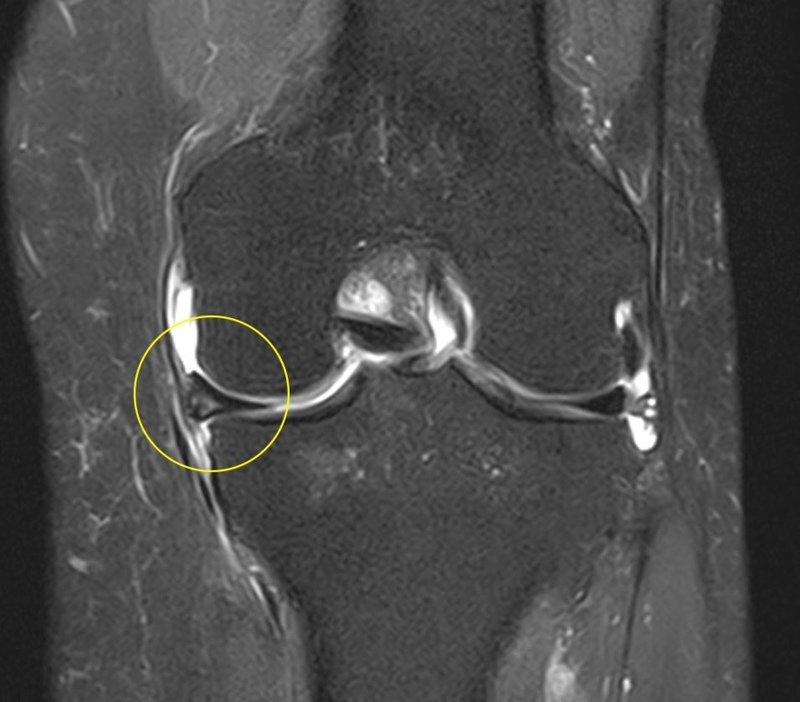

MRI検査

練習を一定期間休むとはれはなくなるが運動量をあげると腫れが出現してしまい試合出場が困難な状態となり治療のため帰国した。XP画像

20代女性海外プロサッカーリーグの選手の例

PRP治療

目的:膝の炎症症状の改善と組織修復リハビリテーション

結果

サッカーを行なっても腫れが出現しなくなり無事試合に復帰した。11.痛みの原因は1つではない